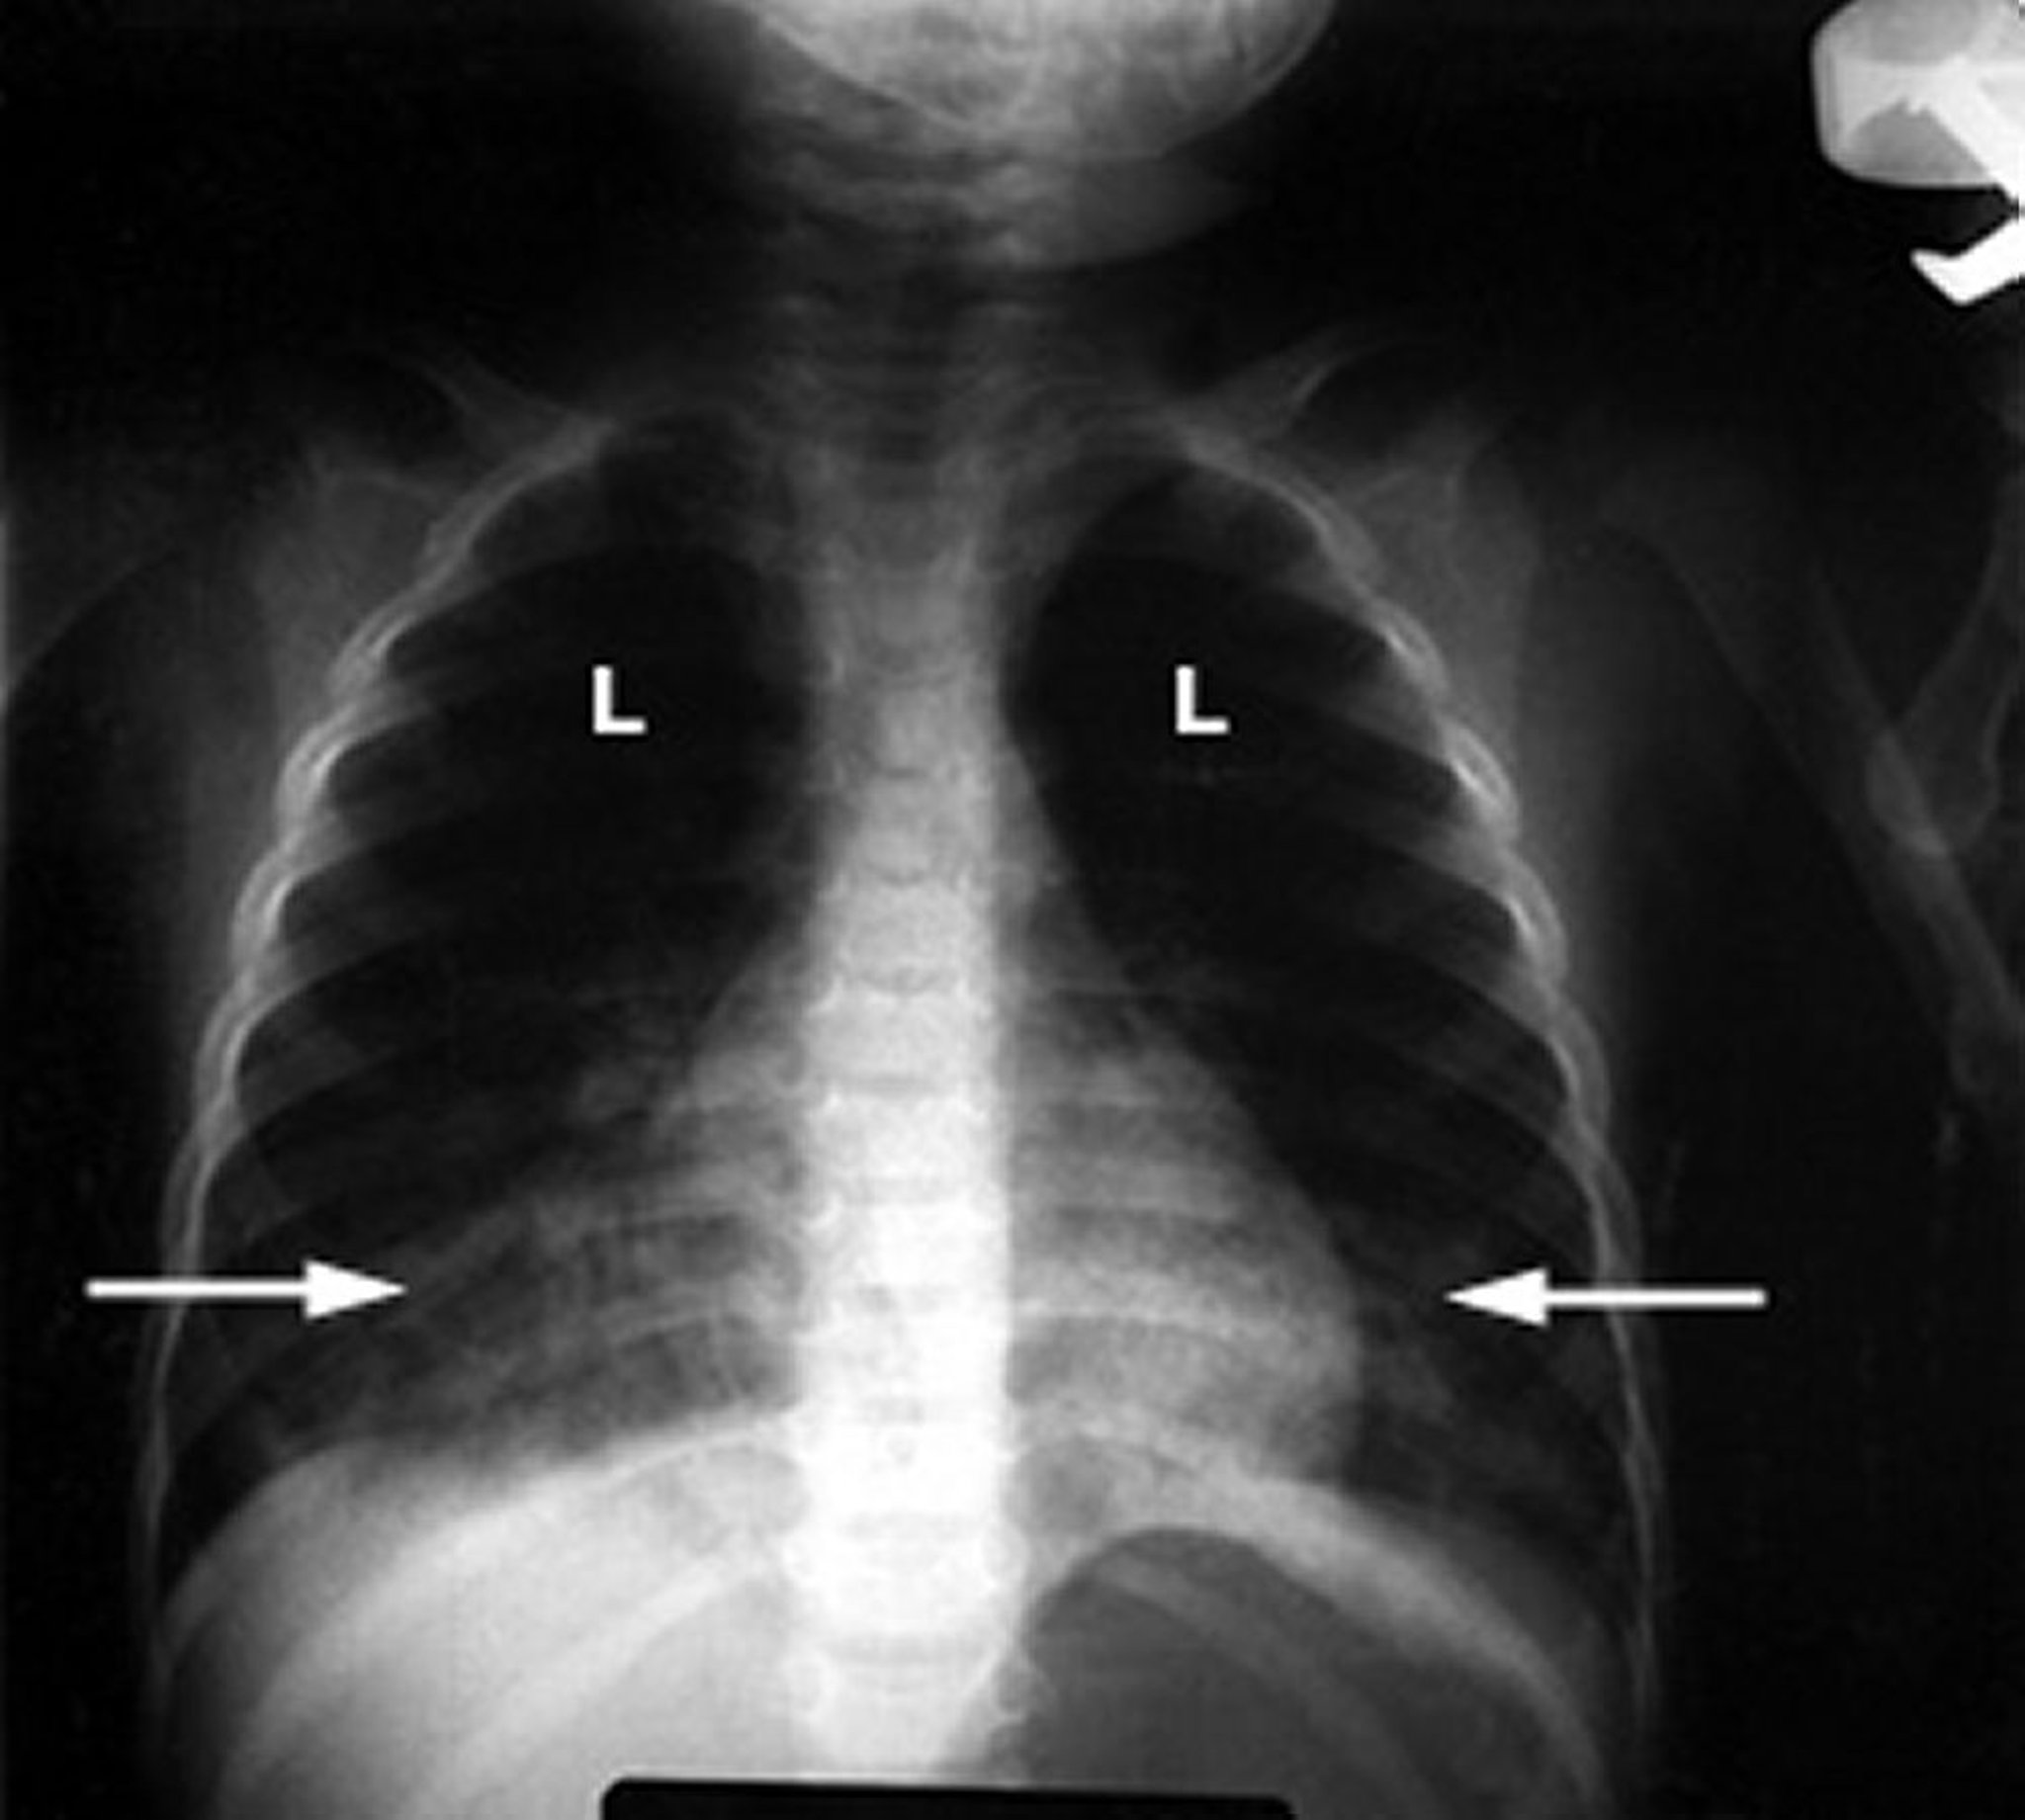

A intoxicação por hidrocarbonetos é diagnosticada a partir da descrição do sucedido e do odor característico de petróleo no hálito da pessoa ou no vestuário ou se for encontrado um recipiente perto da pessoa. Resíduos de tinta nas mãos ou em torno da boca podem sugerir que a pessoa esteve recentemente cheirando tinta. A pneumonia e a pneumonite química são diagnosticadas com uma radiografia do tórax e medindo-se a concentração de oxigênio no sangue (consulte Análise de gasometria arterial). Se o médico suspeitar de danos cerebrais, é realizado um exame de ressonância magnética (RM).